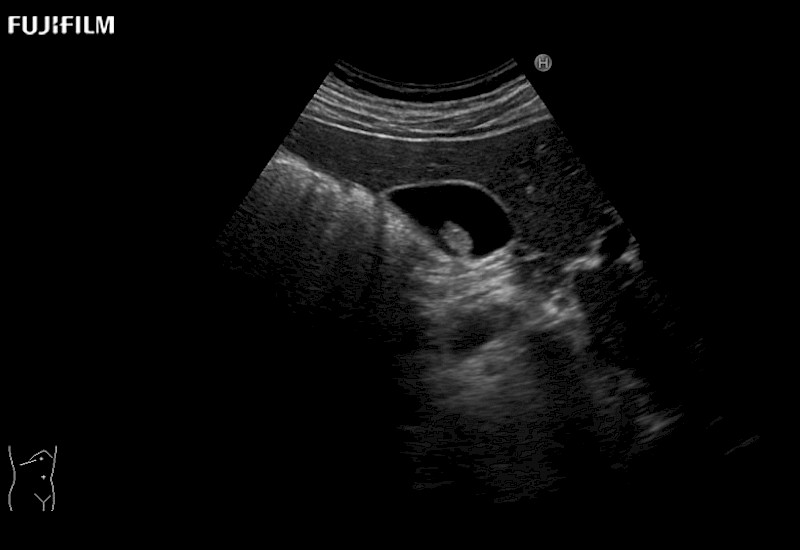

Extraordinary high-resolution digital imaging

for use during open and laparoscopic procedures: Tumor localization & staging, Ablation, Resection, Biopsy, Transplant, Abdominal exploration, Robotic surgery

- Exceptional near and far-field resolution

- Instant feedback on tumor margin delineation

- Valuable information to guide tumor resections

C9150LA - 4-way Laparoscopic Transducer

Curved array 4-way laparoscopic transducer for better visualization of targeted lesions.

- Built to withstand the rigors of daily laparoscopic surgery

- Ideal for liver and kidney scanning

- Exceptional near and far-field resolution

- Instant feedback on tumor margin delineation

L44LA - 4-way Laparoscopic Transducer

Exclusive linear array 4-way laparoscopic transducer for better visualization of targeted lesions.

- Built to withstand the rigors of daily laparoscopic surgery

- Ideal for liver and kidney scanning

- Exceptional near and far-field resolution

- Instant feedback on tumor margin delineation

L44LA1 - Rigid Laparoscopic Transducer

Exclusive linear array rigid laparoscopic transducer for better visualization of targeted lesions.

- Built to withstand the rigors of daily laparoscopic surgery

- Preferred transducer for liver RFA and biopsies

- Exceptional near and far-field resolution

- Instant feedback on tumor margin delineation